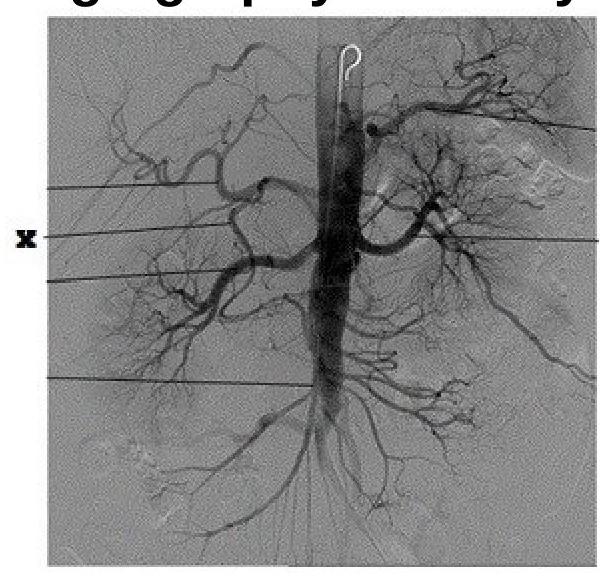

Identify the artery labeled as 'X' in the provided angiography anatomy image.

Explanation: ***Superior mesenteric artery*** - The image displays a selective angiogram highlighting an artery branching off the **aorta** in the abdominal region and supplying multiple loops of bowel, characteristic of the superior mesenteric artery. - The location and extensive branching pattern supplying various abdominal structures confirm its identity as the **superior mesenteric artery**, which typically arises below the celiac trunk. *Subclavian artery* - The **subclavian artery** is located in the chest and shoulder region, supplying the upper limbs and parts of the head and neck. - Its anatomical location and distribution are distinctly different from the abdominal artery shown in the image. *Celiac trunk* - The **celiac trunk** is an earlier branch off the aorta, typically arising just below the diaphragm, and it branches into the splenic, left gastric, and common hepatic arteries. - The artery labeled 'X' arises lower than where the celiac trunk would typically originate and demonstrates a different branching pattern. *Brachiocephalic trunk* - The **brachiocephalic trunk** (also known as the innominate artery) is a major artery in the upper chest, typically the first branch off the aortic arch. - It supplies blood to the right arm and head, not abdominal organs, making it anatomically incorrect for the artery labeled 'X'.